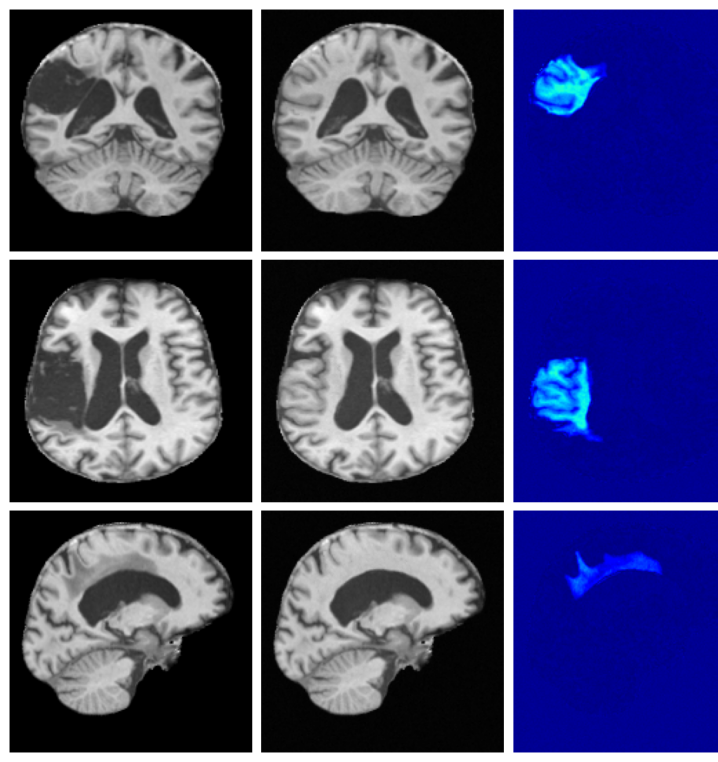

Qualitative T1w results are shown in Figure 2, with further examples for other modalities in Appendix A.8. LoHiResGAN and Res-SRDiff produce unrealistic images with severe artifacts, likely arising from bias fields, sharp intensity artifacts, and other noise not present during training. UniRes generates oversmoothed images, likely due to its TV prior and its reliance on information from multiple input modalities, whereas we apply it unimodally. SynthSR, like our method, preserves key anatomical structures; however, our difference maps show reduced contrast, further supporting the strong quantitative results shown in Table 1.

A.8 Additional qualitative restoration results

Additional qualitative results for the Clinical dataset are given in Figures 7, 8 and 9, and for the Low-field dataset in Figures 10 and 11.